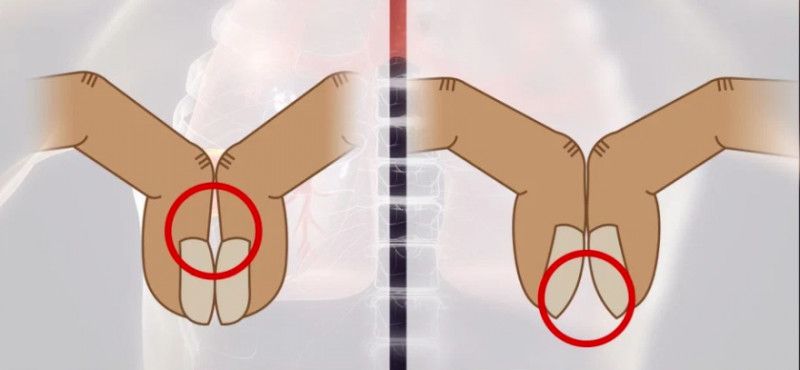

Testul implică alăturarea unghiilor de la degetul arătător pentru a verifica dacă între cuticule există un spațiu, care are cel mai des forma unui diamant, în cazul unei persoane care nu suferă de cancer la plămâni, potrivit Huffington Post.

Dacă nu există niciun spațiu între cuticule, acesta este un semn foarte comun al cancerului la plămâni. Astfel că dacă o persoană descoperă că nu are acest spațiu, ar trebuie să facă o vizită la medic pentru verifica sănătatea plămânilor. Acesta poate fi un simptom timpuriu al unei afecțiuni care deseori este fatală: cancerul la plămâni.